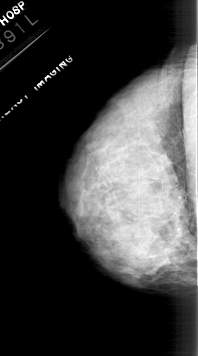

A_1113_1.LEFT_CC

LEFT_CC LINES 4621 PIXELS_PER_LINE 2566 BITS_PER_PIXEL 12 RESOLUTION 43.5 NON_OVERLAY